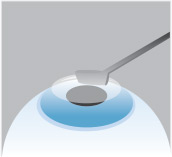

Step 1

Alongside numbing drops, an alcohol solution is placed on the eye to help soften the cornea.

Step 2

The surgeon then smooths the surface of the cornea with a special surgical instrument.